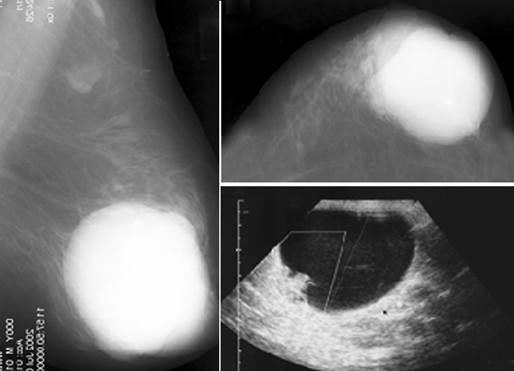

При выявлении микрокальцинатов полученные данные хуже данных маммографии. В целом, по разным данным, диагностическая точность УЗИ не превышает 87% (рис. 1).

Рисунок 1. Разные лучевые методы в диагностике РМЖ